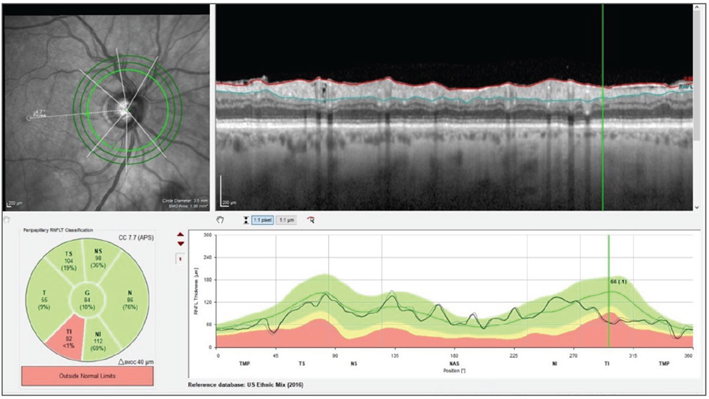

In this case study, Dr. James Fanelli describes how a sudden, dramatic change in a glaucoma patient’s visual field initially raised concerns about disease progression but was ultimately traced to upper eyelid dermatochalasis obstructing the patient’s vision—an observation made through a physical exam and conversation about patient habits. Heidelberg Engineering imaging technology allowed the clinician/the doctor to further confirm structural stability, demonstrating the importance of combining advanced imaging with clinical observation in glaucoma management.

Image courtesy: James L. Fanelli, OD